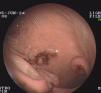

Durante su estudio, presentó dolor abdominal y melenas, por lo que se realizó una endoscopia gastroduodenal donde se visualiza la presencia de 3 tumoraciones con cráter central, ulcerado, leñoso, con bordes elevados rodeados de mucosa macroscópicamente normal (fig. 2). Estudio histológico: linfoma no Hodgkin tipo B gástrico. Inmunohistoquímica: CD-20 positivo. CD-3, CD-5, CD-10, CD-30, BCL-2 y Ki-67, negativos. Mapa óseo, citología del LCR y aspirado y biopsia de médula ósea, normales.